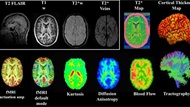

Traumatic Brain Injury Center of Excellence

Icon for TBICoE

TBICoE supports the MHS and DHA with traumatic brain injury research initiatives, including gap-driven analyses and congressionally directed programs such as the 15-year longitudinal study of TBI and an investigation into the effects of blast exposure on Warfighter Brain Health and Performance.